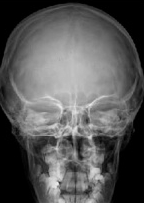

Estructuras Anatómicas Visibles

Hueso Frontal

Región frontal completa

Crista Galli

Apófisis etmoidal

Celdas Etmoidales

Posteriores etmoidales

Peñascos

Porción petrosa temporal

Temporales

Huesos temporales

Calidad de Imagen

Simetría perfecta, bordes óseos nítidos, diploe visible.